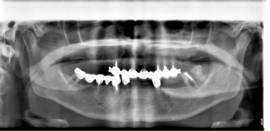

מתרפאה תושבת חוץ כבת 57 עם חוסר שיניים חלקי בשתי הלסתות. שאר השיניים הקיימות ניידות ואבודות , איכות הלעיסה ומראה החיוך ירודים מאוד.

בלסת העליונה ביצענו עקירות כל השיניים בישיבה אחת עם הרמות סינוס משני הצדדים והתקנת 11 שתלים. בפגישה נוספת עבור הלסת התחתונה נעקרו גם כן כל השיניים עם ביצוע מיידי של 10 שתלים.

מייד בתום ההשתלות בכל לסת בוצעה העמסה מיידית עם גשרי אקריל זמניים שהוכנו מראש וסיפקו מענה תפקודי ואסטטי מצויין לתקופת ההמתנה.

בישיבה אחת לכל לסת בוצעו כל העקירות ,כל ההשתלות והתקנת גשר האקריל על מנת לאפשר למתרפאה לצאת עם שיניים בו ביום.

לאחר 6 חודשים וקליטת השתלים באופן מלא, קיבלה המתרפאה גשרי חרסינה קבועים ברמת דיוק ואסטטיקה מושלמים.